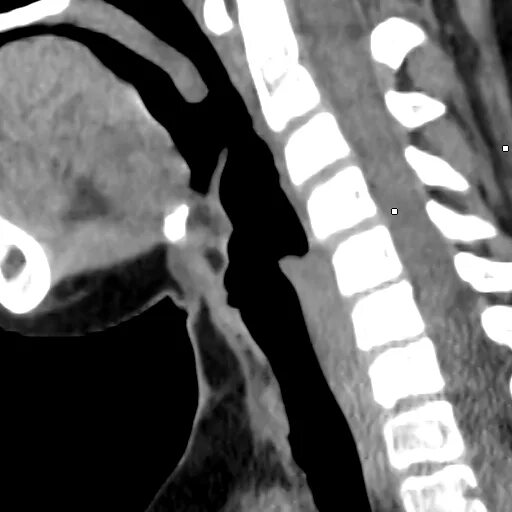

Грыжа шейного мкб